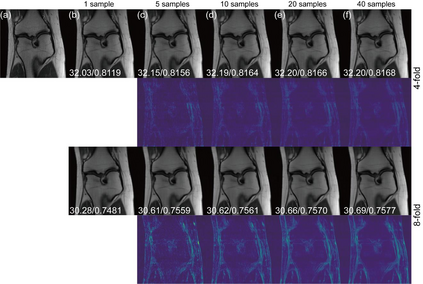

Deep learning-based MRI reconstruction models have achieved superior performance these days. Most recently, diffusion models have shown remarkable performance in image generation, in-painting, super-resolution, image editing and more. As a generalized diffusion model, cold diffusion further broadens the scope and considers models built around arbitrary image transformations such as blurring, down-sampling, etc. In this paper, we propose a k-space cold diffusion model that performs image degradation and restoration in k-space without the need for Gaussian noise. We provide comparisons with multiple deep learning-based MRI reconstruction models and perform tests on a well-known large open-source MRI dataset. Our results show that this novel way of performing degradation can generate high-quality reconstruction images for accelerated MRI.